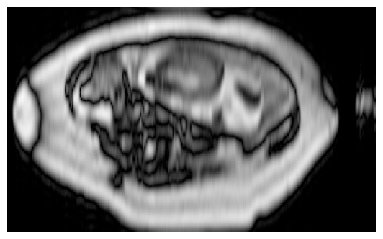

Dynamic free-breathing fetal cardiac MRI is one of the most challenging modalities, which requires high temporal and spatial resolution to depict rapid changes in a small fetal heart. The ability of deep learning methods to recover undersampled data could help to optimise the kt-SENSE acquisition strategy and improve non-gated kt-SENSE reconstruction quality. In this work, we explore supervised deep learning networks for reconstruction of kt-SENSE style acquired data using an extensive in vivo dataset. Having access to fully-sampled low-resolution multi-coil fetal cardiac MRI, we study the performance of the networks to recover fully-sampled data from undersampled data. We consider model architectures together with training strategies taking into account their application in the real clinical setup used to collect the dataset to enable networks to recover prospectively undersampled data. We explore a set of modifications to form a baseline performance evaluation for dynamic fetal cardiac MRI on real data. We systematically evaluate the models on coil-combined data to reveal the effect of the suggested changes to the architecture in the context of fetal heart properties. We show that the best-performers recover a detailed depiction of the maternal anatomy on a large scale, but the dynamic properties of the fetal heart are under-represented. Training directly on multi-coil data improves the performance of the models, allows their prospective application to undersampled data and makes them outperform CTFNet introduced for adult cardiac cine MRI. However, these models deliver similar qualitative performances recovering the maternal body very well but underestimating the dynamic properties of fetal heart. This dynamic feature of fast change of fetal heart that is highly localised suggests both more targeted training and evaluation methods might be needed for fetal heart application.